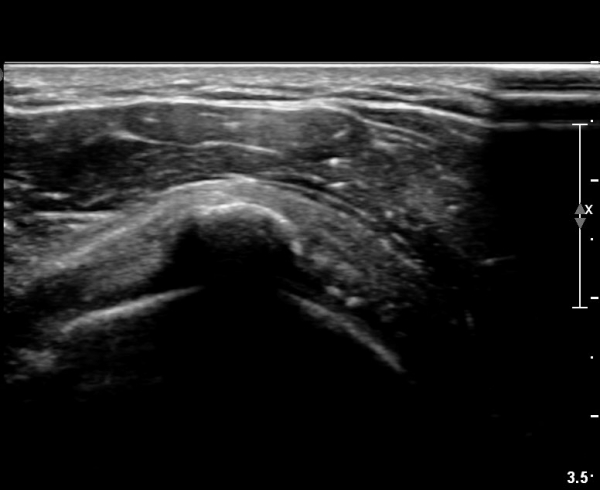

±Ø»ó°Ç Á¾´Ü¸é °Ë»ç»ó¿¡¼­ Á¡¾×³¶³»¿¡ ÁÖ»ç¹Ù´ÃÀÌ À§Ä¡ÇÑ °ÍÀÌ º¸ÀδÙ(»çÁø 3).

Á¡¾×³¶³» ÁÖ»ç ÈÄ ÁÖ»ç¹Ù´ÃÀ» ¹Ýº¹ÀûÀ¸·Î ´õ ÁøÀÔ½ÃÄÑ ¼®È¸¸¦ ºÐ¼âÇÑ´Ù(»çÁø 4).